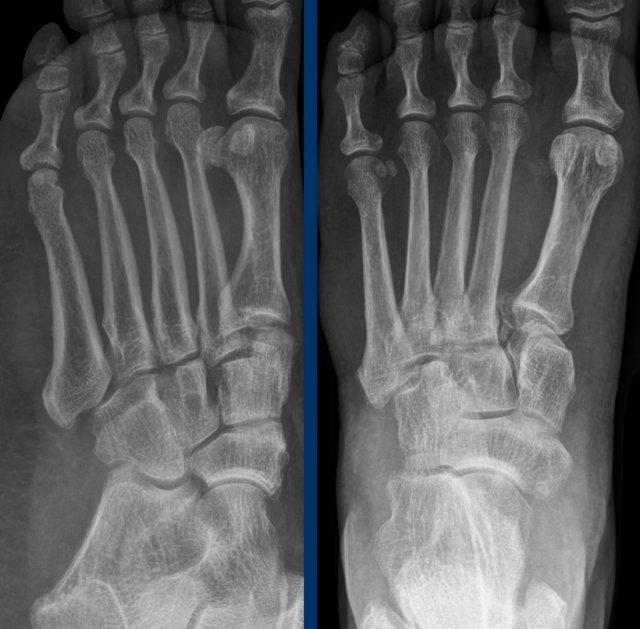

Ca 1 – Chấn thương bàn chân

Bệnh nhân 33 tuổi bị chấn thương bàn chân và sưng nề vùng giữa bàn chân.

Nhấp vào hình ảnh để xem phóng to.

Hình ảnh cho thấy những dấu hiệu gì và có ý nghĩa như thế nào?